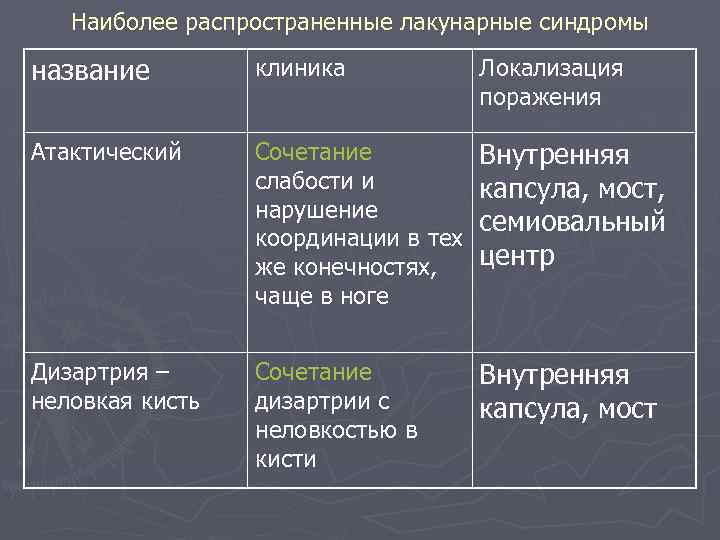

Наиболее распространенные лакунарные синдромы название клиника Локализация поражения Атактический Сочетание слабости и нарушение координации в тех же конечностях, чаще в ноге Внутренняя капсула, мост, семиовальный центр Дизартрия – неловкая кисть Сочетание дизартрии с неловкостью в кисти Внутренняя капсула, мост